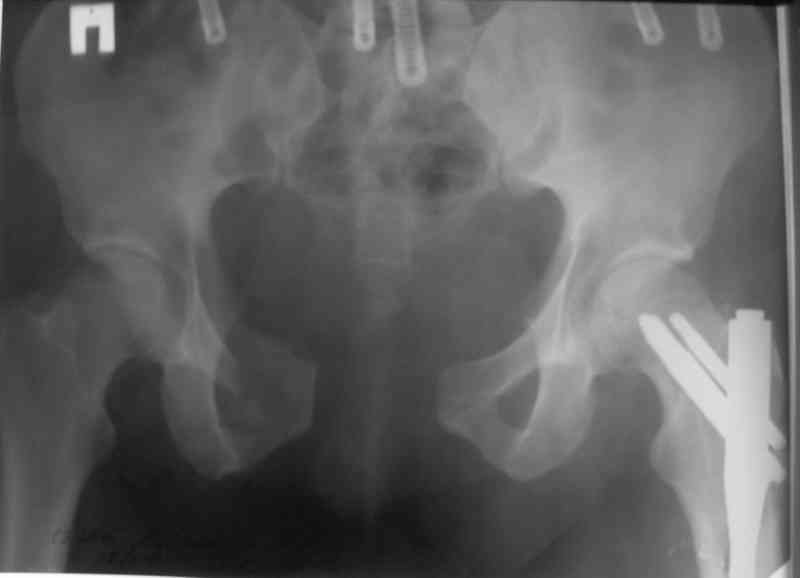

в результате обсуждения у меня образовался следующий план: При удачной попытке непрямой репозиции на тракционном столе я бы остановился

на фиксакции каннюлированными винтами Правого КП сочленения и длинные Шанц винты( как предложил Джолдас) , дающие стабилизацию и переднего отдела и КП сочленений.

При неудачной репозиции, видимо, придется открываться из переднего доступа по Симпсону и репонировать смещенную вверхи и кзади подвздошную кость с помощью 2-3 holes DCP,затягивая винты на подвздошной кости должны устранить её смещения и стержневой аппарат для стабилизации переднего полукольца.

Поскольку готового плана фиксации таза у меня не было (состояние больного стабильное, стабилизировать таз аппаратом сразу не стал ввиду риска инфекции при возникновении необходимости открытой репозиции) в первую сессию

зафиксировал бедро и лодыжку.